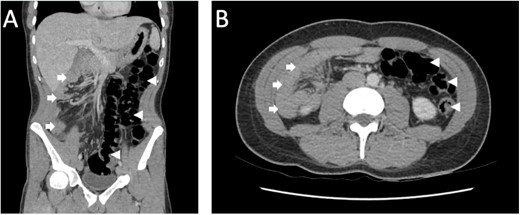

A 28-year-old male was referred for a review of his severe abdominal pain associated with eating, unintentional weight loss and intermittent vomiting and diarrhoea over several years. His background medical history included a laparoscopic converted to open appendicectomy performed overseas when he was an adolescent. Clinical examination and biochemical investigations were unremarkable. Computed tomography (CT) of the abdomen demonstrated features of intestinal malrotation, with the entirety of the large bowel on the left and the small bowel on the right, without any evidence of acute obstruction (Fig. 1).

CT abdomen/pelvis in the portal venous phase (A) coronal, (B) axial demonstrating features of intestinal malrotation with the colon (arrowhead) predominantly located on the left and the small bowel (arrow) on the right.